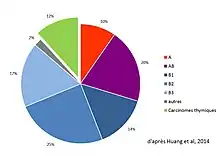

Les tumeurs épithéliales thymiques sont classées selon la classification de l'OMS réactualisée en 2003, puis en 2015[46],[47] en thymomes (de type A, AB, B1, B2 ou B3) et carcinomes thymiques[48]. Les tumeurs neuroendocrines thymiques sont encore une autre entité, très rare (moins de 5 % des tumeurs thymiques et moins de 200 cas rapportés[14]), décrite en 1972[49]. Un consensus international publié en 2014 par le groupe ITMIG précise les critères permettant de définir exactement les sous-types histologiques[46].

Épidémiologie

Les types B2 sont les plus fréquents thymomes avec 25 à 28 % du total, et le type B1 est le plus rare (10 à 12 %)[39]. La répartition des types histologiques varie avec l'âge (les types A et AB sont plus fréquents chez les patients de plus de 55 ans), mais pas avec le sexe.

On observe des variations dans la répartition géographique, les types A et B2 étant moins fréquents en Asie qu'en Europe et en Amérique du Nord, au contraire des types AB et B3. Les thymomes B1 sont en revanche répartis de manière harmonieuse entre ces régions. Il n'existe cependant pas de données pour le continent africain[51].